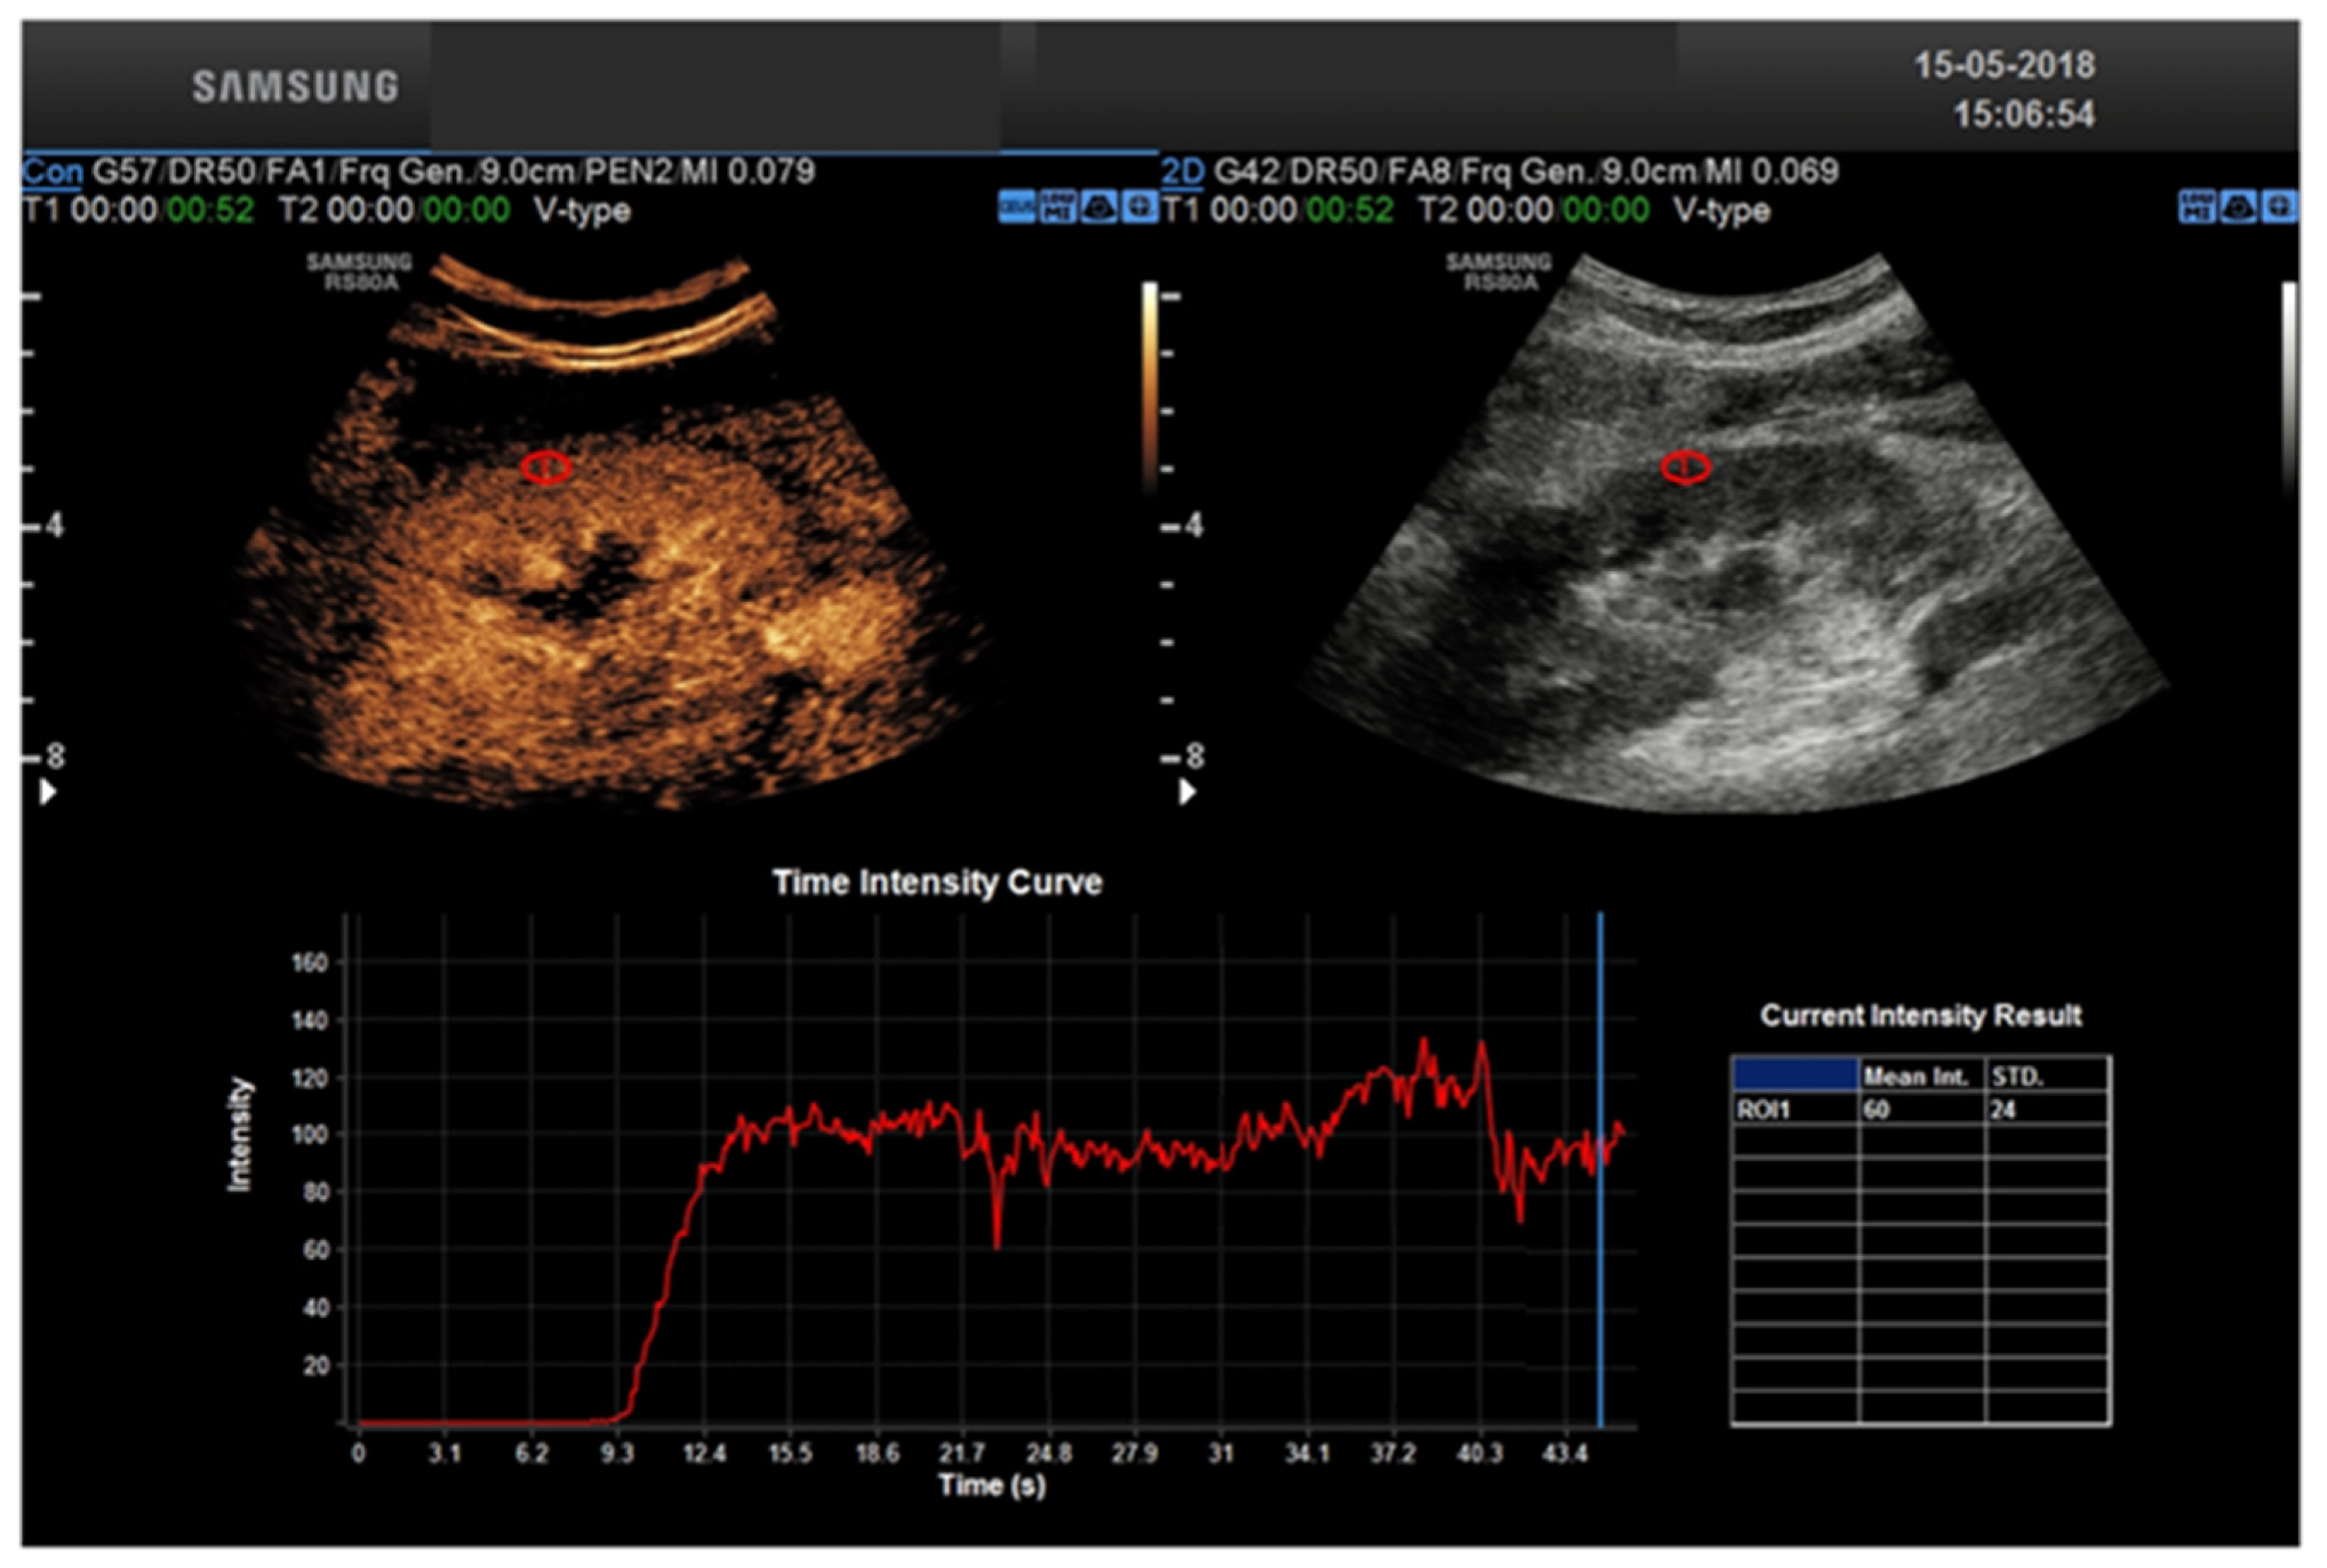

CEUS allows a real-time assessment of contrast enhancement, with the ability to record the entire real-time, high frame rate examination as a cine-loop for review. Real-time acquisition allows for the representation of the cortico-medullary phase in all examinations, independently from the patient’s hemodynamic status, without the need for bolus tracking. Continuous data acquisition allows for time-intensity curves evaluating contrast enhancement intensity versus time, from which extracting quantitative indexes of perfusion is possible with the appropriate software [23].

KT remains the most effective method of treatment for ESRD, reducing the mortality rate and improving the quality of life compared to the alternative of chronic dialysis [4]. However, despite the advances in surgical techniques and immunosuppression therapy, significant post-transplant complications in KT recipients may occur [5]. CEUS represents a powerful tool to improve the speed and cost-effectiveness of the diagnostic work-up after KT. US is portable and can be used at the patient’s bedside, avoiding transporting critically ill patients from the intensive care unit to the radiology department. The transplanted kidney examination in the iliac fossa can be performed rapidly and without the need to control respiration. This is an extraordinary benefit compared to more time-consuming imaging techniques, especially MRI. CEUS uses a non-renal toxic contrast media based on microbubbles of an inert gas, i.e., sulfur hexafluoride or perfluorocarbons, which are shattered by the high-energy ultrasound waves, thus providing information about flow and tissue perfusion. Compared to contrasts used in CT or MRI, they are pure intervascular agents that do not extravasate into the vascular system. They are non-nephrotoxic and can be safely tolerated in patients with renal impairment or renal occlusion [40]. Contrary to CE CT or MRI, in which the acquisition is performed at definite time-points (i.e., snap shots in time), CEUS provides a real-time, high frame rate representation of contrast distribution, with the ability to record the entire contrast examination with dynamic cine-loops. Real-time acquisition allows a correct representation of the cortico-medullary phase in all examinations, independently from the patient’s hemodynamic status, without the need for bolus tracking. Continuous data acquisition can be also translated into time-intensity curves (TIC), plotting contrast enhancement intensity versus time, which in turn are the bases for extracting quantitative indexes of perfusion with the proper software [22] (Figure 2 and Figure 3). To summarize: CEUS represents an ideal first-line tool in evaluating KT patients, improving the accuracy of conventional US for a variety of complications. However, it is not free from limitations: CEUS requires skilled operators and is also less panoramic than CT and MRI. Additionally, not all patients are eligible such as uncooperative patients. CT may be considered a complimentary tool in the evaluation of RT complications. In patients with a satisfactory renal function, contrast-enhanced CT angiography (CTA) can be used to assess and treat a renal artery stenosis. Furthermore, in the delayed acquisition, contrast-enhanced CT can be used to confirm or exclude a urinary leakage or urinoma. Non-contrast CT may be helpful to assess the extent of a perinephric fluid collection and its relationship to the adjacent structures. Finally, unenhanced CT performs a better assessment of renal and ureteral stones than US, especially for small stones [41,42].

Figure 2.

Healthy kidney TIC.

Figure 3.

Ischemic Kidney TIC.